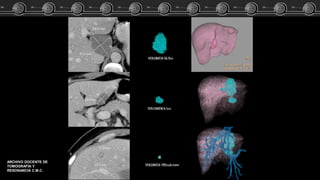

Malformacion A-V?? Caso Clínico

Las MAV pueden estar

ocasionadas por trastornos

hereditarios que ocasionan

displasia fibrovascular.

Grandes arterias tortuosas intra y

extrahepaticas.

Realce heterogéneo del

parénquima hepático.

Pueden simular masas.

DIANOSTICO POR IMAGEN.

ABDOMEN. FEDERLE.

2011.